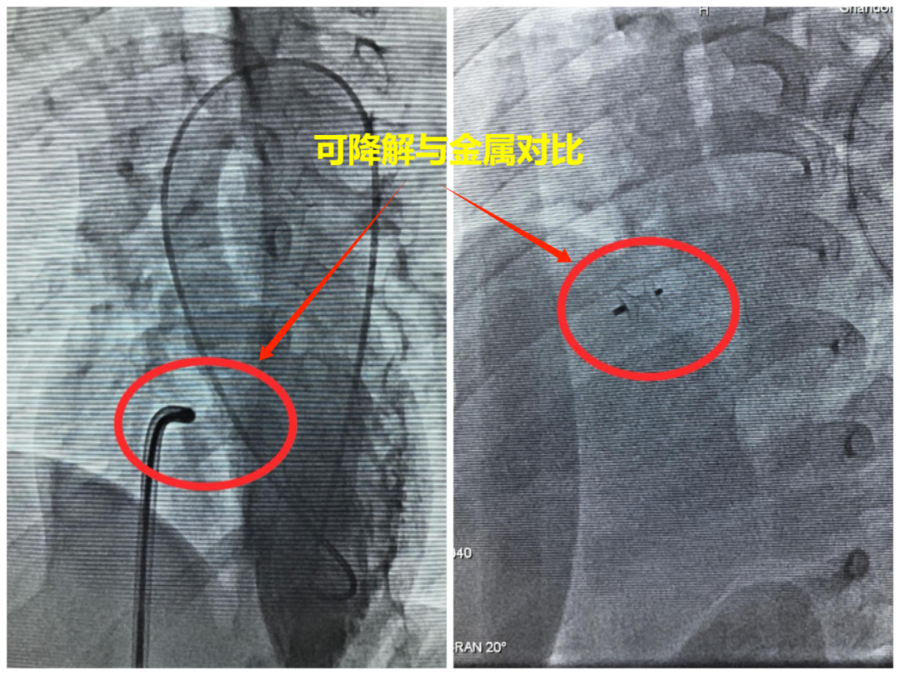

室间隔缺损是儿童常见的先天性心脏病之一,若不及时治疗,可能导致患儿生长发育迟缓、反复肺部感染,甚至引发心力衰竭等严重并发症。传统的治疗方式多采用金属封堵器介入治疗,虽能有效封堵缺损,但金属异物需终身留存体内。可降解室间隔缺损封堵器,是目前国际上先进的微创介入治疗器械。该封堵器由生物可降解材料制成,在植入体内后,能迅速封堵心脏缺损,恢复正常血流动力学。随着时间的推移(通常1年),封堵器会逐渐被人体吸收降解,最终完全消失,避免了金属封堵器长期留存体内可能带来的潜在风险,为患儿的长远健康提供了更可靠的保障。

在过去的一段时间里,济南市儿童医院心血管内科李磊主任带领团队,凭借丰富的临床经验、精湛的介入技术和高度的责任心,成功为患儿实施了可降解封堵器植入手术。这些患儿年龄从2岁到9岁不等,术前经详细检查评估,均符合可降解封堵器治疗指征。手术在导管室进行,手术在超声引导下,医生通过股静脉或股动脉穿刺,将纤细的导管送达心脏缺损部位,精准释放可降解封堵器。整个手术过程创伤小、时间短,患儿术后恢复快,1周便顺利出院。